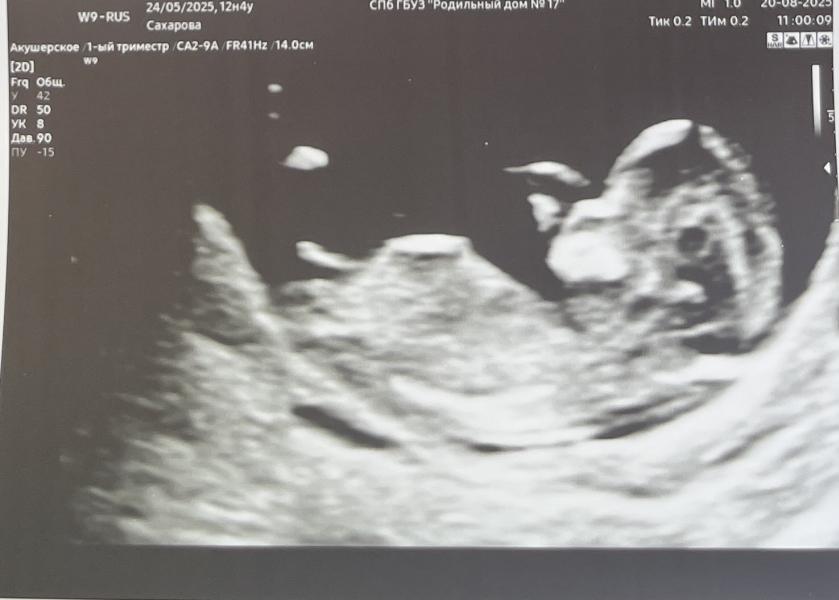

1 скрининг пройден ✅. ПДР 7 марта.

11 недель 4 дня